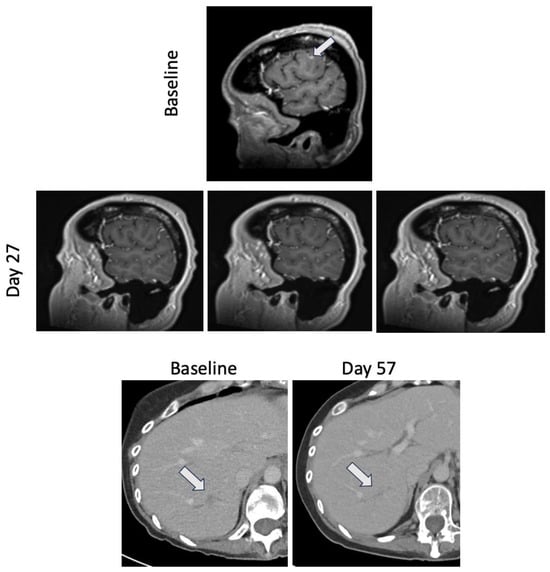

2. Case Report